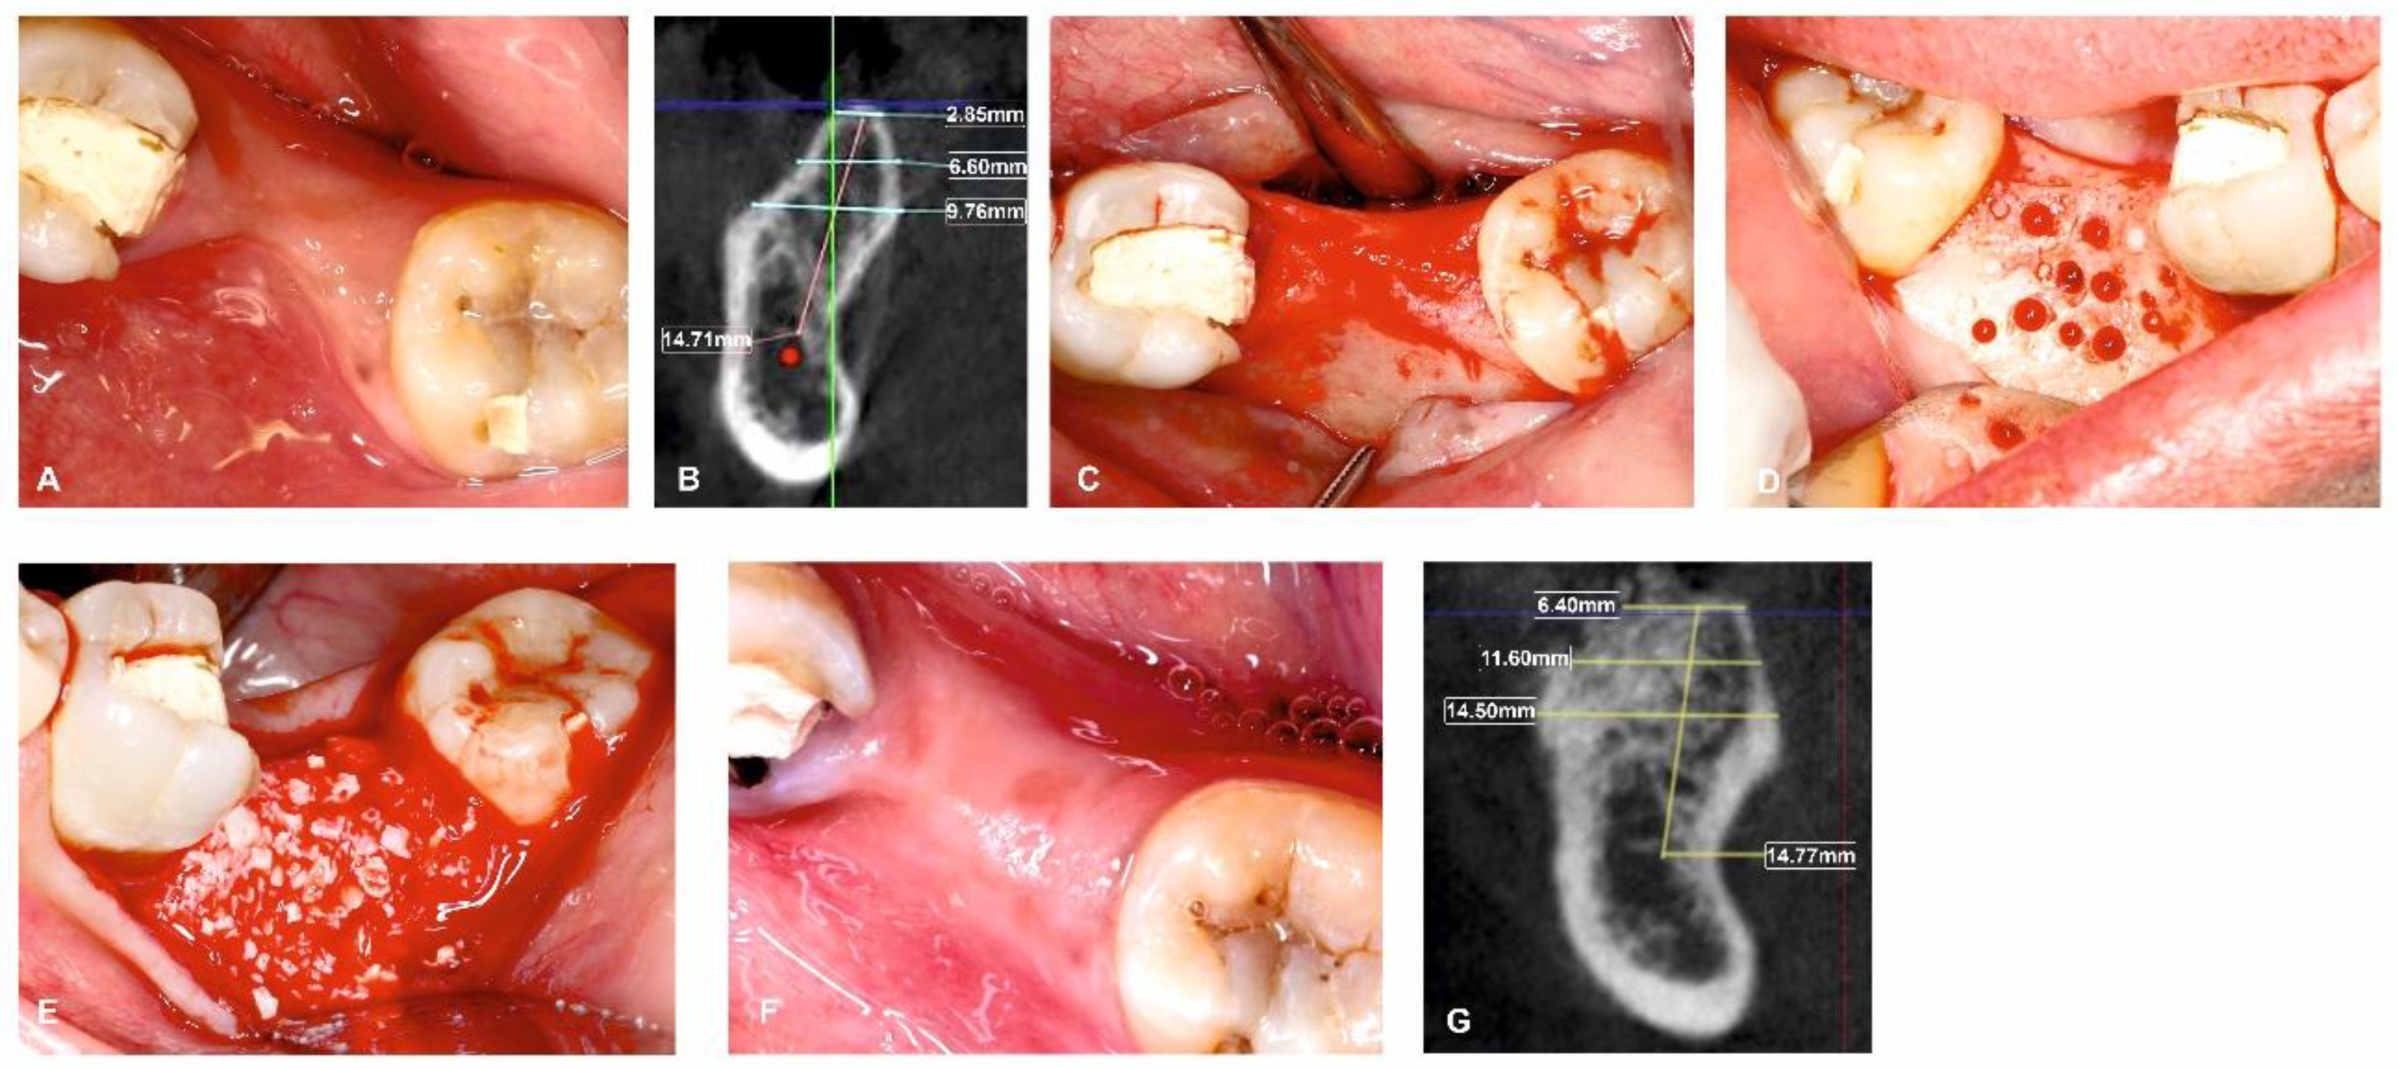

Figure 3.

Surgical management of horizontal ridge defect (group-II). (A) Preoperative horizontal ridge deficient site; (B) HRW and VBH measurements assessed at crest, at 3 mm, and at 6 mm in baseline; (C) Flap elevation; (D) Decortications performed in the surgical site; (E) Sticky bone placement; (F) 6-month follow-up; (G) HRW and VBH measurement assessed at crest, at 3 mm, and at 6 mm at 6 months.

All surgical procedures were carried out by a single, trained periodontal surgeon (H.P). For both Group I and Group II, local anaesthesia was administered using 2% lignocaine with adrenaline. After performing a mid-crestal incision through the keratinized gingiva, a full-thickness flap was raised on the buccal and lingual side. To enable osteoprogenitor cell migration, multiple neo-angiogenetic cortical holes were made in the recipient bone bed. A total of 10 mL of venous blood obtained from the antecubital vein in non-coated plastic vacutainers was immediately spun in a centrifuge at a pre-programmed spin to obtain i-PRF (700 rpm for 3 min with 60 g force) (Dentifuge LC-100). The prepared i-PRF was mixed with ABBM (Bio-OSSTM, Geistlich®, Zurich, Switzerland) (Figure 1); polymerisation takes approximately 5–10 min, resulting in sticky bone formation [22,23,24]. In Group I, sticky bone was adapted and moulded over the defect to the level of the adjacent neighbouring buccal bony contour. A bi-layered cross-linked collagen membrane (Cologide™, Cologenesis Healthcare Pvt Limited) of adequate size was chosen and cut to fit the defect size, and it was employed to cover the bone grafts with a 2 mm overlap buccally (Figure 2A–H) and on the lingual side the membrane was tucked inside the lingual flap; in Group-II, the same protocol as Group-I was followed, with the placement of the prepared sticky bone without the collagen membrane (Figure 3A–H). Tension-free primary closure was achieved with simple, interrupted (3-0 Vicryl, Ethicon) sutures in both groups. Six months after the augmentation, cone beam-computed tomographic (CBCT) images were taken.